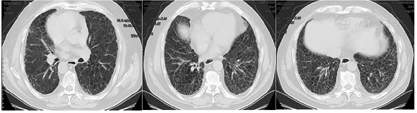

患者经治疗后肿瘤病灶明显缩小(图3,图4,图5,图6,图7,图8),定期于我院随访复查,目前一般情况良好,未见复发及远处转移。

PD-L1是一种跨膜糖蛋白,属于B7家族成员之一,一级结构包括290个氨基酸,亦由胞外区、疏水跨膜及尾部胞浆区组成[2]。有研究发现,PD-L1蛋白广泛表达于活化T淋巴细胞、巨噬细胞、B细胞等免疫细胞,还表达于多种类型的恶性肿瘤细胞表面,比如乳腺癌、胶质瘤、恶性黑色素瘤等[3]。PD-L1与其受体程序性死亡分子1 (PD-1)结合形成PD-1/PD-L1通路,该通路可介导形成机体的免疫抑制微环境,参与肿瘤细胞的免疫逃逸,继而促进肿瘤的发展。研究发现,27%~50%的肺癌患者可表达PD-L1[4,5],Koh等人[6]发现,在肺腺癌组织中PD-L1的阳性表达率为59%,且其阳性表达与患者淋巴结转移、组织分化程度及吸烟有关。有研究结果表明,肺鳞癌组织PD-L1阳性表达明显高于正常肺组织,PD-L1阳性表达与患者pTNM分期、淋巴转移有关,提示PD-L1在肺鳞癌的发生、进展过程中具有重要作用[3]。但目前单独研究PD-L1对肺鳞癌患者预后影响的报道甚少,尤其是伴有肺间质纤维化的肺鳞癌患者的相关研究更少,有待于大规模的临床试验。PD-L1抑制剂虽然可以达到预期的抗肿瘤效果,但这是一个非常复杂的过程,也有发生免疫相关不良事件的风险,包括诱发各种器官的炎症反应[7,8]。目前,其背后的机制仍不清楚,但先前的肺部疾病可能是免疫检查点抑制剂诱发肺炎的一个危险因素[9],所以由于肺炎的风险增加,肺间质纤维化合并肺癌患者接受免疫检查点抑制剂治疗的报道甚少。在以往的研究中,与传统非小细胞肺癌的化疗方案相比,抗PD-1治疗导致重度免疫相关性肺炎的发生率较高,但抗PD-L1治疗则不然[10]。也有研究显示,使用PD-1抑制剂患者3/4级免疫相关性肺炎的发生率仅略高于使用PD-L1抑制剂的患者[11]。此例病人为肺鳞状细胞癌伴肺间质纤维化,肿瘤细胞的PD-L1阳性表达百分比高达78%,因此在GP方案化疗的同时联合应用PD-L1抑制剂度伐利尤单抗,并在化疗与免疫联合治疗5疗程后以度伐利尤单抗单药维持。复查时可见右肺下叶的肿瘤病灶迅速且明显缩小,肺间质纤维化未见进展。患者治疗初期躯干部有散在皮疹出现,经抗过敏治疗后皮疹消失。患者1年半来复查病情稳定,未见复发及除淋巴结以外的其他部位转移,没有报告过除散在皮疹以外的免疫相关不良事件发生,也进一步证实了肺鳞癌病人化疗联合抗PD-L1药物作为一线治疗方案的可行性和安全性,为临床工作中肺鳞癌病人的治疗提供了新的思路。但目前病例数少,有待于大规模的临床试验。我们期望,在不远的未来,免疫治疗可使越来越多的肺癌患者获益。